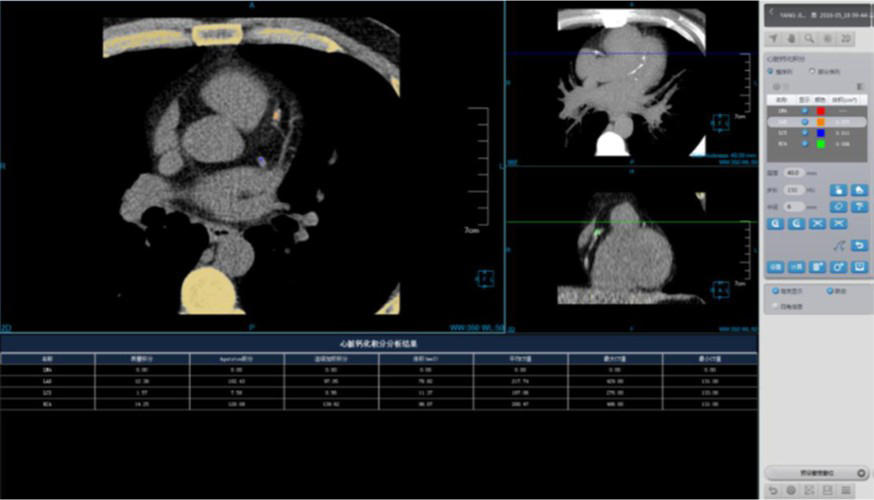

Coronary Calcium Scoring

Estimate the amount of calcium in the coronary arteries

• Agatston score

• Volume score

• ROI information calculation